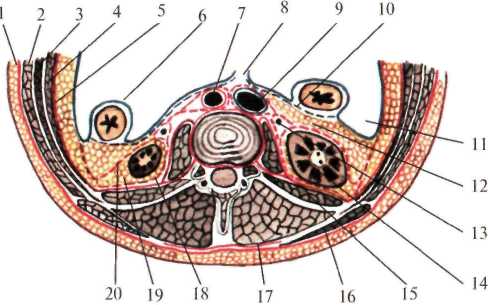

Околопочечная жировая клетчатка заключена между листками почечной фасции (fascia renalis). Эта фасция вверху начинается на уровне X-XI ребер, с боков – от места перегиба париетальной брюшины, затем, расщепившись на два листка (fascia retrorenalis et fascia praerenalis), охватывает околопочечную жировую клетчатку (рис.2.4.).

Околоободочная клетчатка залегает впереди от переднего листка почечной фасции. Она ограничена: сзади – предпочечной фасцией, спереди – задней поверхностью ободочной кишки и листком париетальной брюшины. В верхних отделах околоободочная клетчатка доходит до корня брыжейки поперечной ободочной кишки, внизу заканчивается у слепой кишки справа и у места перехода нисходящей обододочной в сигмовидную ободочную кишку – слева. Кроме того, по задней поверхности восходящей и нисходящей ободочной кишки залегает позадиободочная фасция Толди (fascia Toldi), представляющая собой перерожденный слой соединительной ткани, в эмбриональном периоде служившей брыжейкой кишечника.

Рис. 2.4. Фасции и клетчатка поясничной области на горизонтальном срезе.

1 – fascia propria; 2 – m. obliquus externus abdominis; 3 – m. obliquus internus abdominis; 4 – m. transverses abdominis; 5 – fascia endoabdominalis; 6 – peritoneum; 7 – aorta abdominalis; 8 – mesenterium; 9 – v. cava inferior; 10 – fascia Toldi; 11 – правый боковой канал; 12 – paracolon; 3 – ureter; 14 – ren;

15 – m. quadratus lumborum; 16 – m. latissimus dorsi; 17 – m. erector spinae; 18 – fascia retrorenalis;

19 – paranephron; 20 – fascia prerenalis.